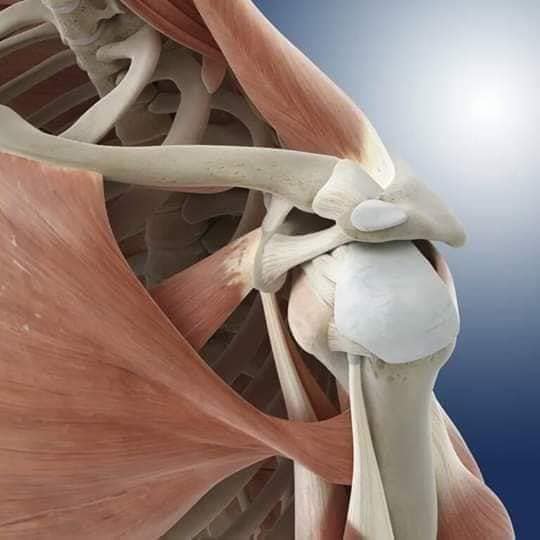

Скелетно-м'язова система людини (синоніми: Опорно-рухова система, опорно-руховий апарат, кістково-м'язова система, локомоторна система) — комплекс структур який утворює каркас, надає форму організму, дає йому опору та забезпечує захист внутрішніх органів і можливість пересування у просторі. Це функціональна сукупність кісток скелета, їх з'єднань (суглобів і сінартрозів), і соматичної мускулатури з допоміжними пристосуваннями, які здійснюють за допомогою нервової регуляції локомоції, підтримання пози, міміки та інших рухових діях, поряд з іншими системами органів утворює людське тіло.

Це саморушний механізм, який складається з 400 м'язів, 206 кісток і декількох сотень сухожиль. Більшість кісток скелету з'єднане рухомо за допомогою суглобів. Одним кінцем м'яз прикріплюється до однієї кістки, утворюючи суглоб, іншим кінцем — до іншої кістки. В англомовній літературі застосовують близькі за значенням терміни: англ. musculoskeletal system (скелетно-м'язова система) та англ. locomotor system (локомоторна система).

М'язи, що піднімають лопатку: Трапецієподібний м'яз: великий м'яз, що покриває верхню частину спини. Його функція - підтримка і рух лопаток, а також забезпечення стабільності хребта.

М'язи, що ведуть лопатку до хребта: Широкий м'яз спини: великий м'яз, що розташований в нижній частині спини. Він відповідає за рухи плечей і лопаток, а також за розширення верхньої частини тулуба.